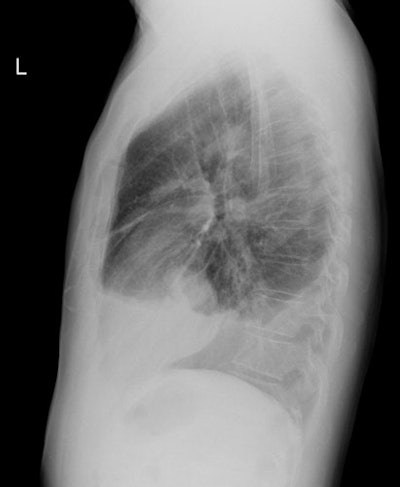

CXR: The lesion usually appears as a markedly thickened, nodular, irregular pleural based mass which coats the pleural surface and grows along fissures. The tumor often encircles the involved lung and is only rarely bilateral. Diffuse pleural thickening can be seen in 60% of cases or pleural masses in 45-60% [15]. Chest wall, diaphragmatic, and mediastinal invasion can be seen with more advanced disease. Contralateral asbestos related pleural disease is seen in 25-50% of cases. A moderate to large, ipsilateral pleural effusion is seen in 50-75% of cases. Because mesothelioma encases the lung it may fix the affected hemithorax so there is no shift away from the side of the tumor, in fact there may be evidence of volume loss on the affected side even in the presence of massive effusion.

Mesothelioma on CXR: Middle aged male presented with chest pain and shortness of breath. CXR demonstrated a moderate to large sized right pleural effusion abnormal nodular thickening of the pleura- particularly evident along the fissures. The patient had no known history of asbestos exposure. |